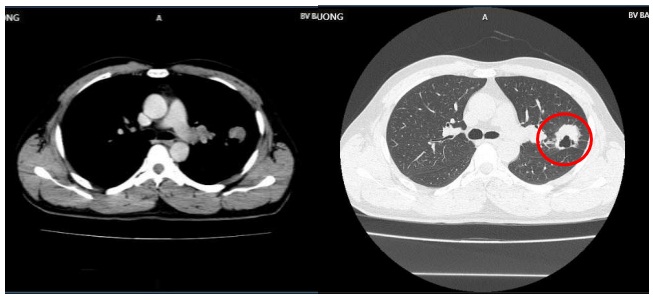

- Cắt lớp vi tính ngực:

Hình ảnh u thuỳ trên phổi trái, kích thước 30x32mm (vòng tròn màu đỏ), vài nốt mờ rải rác màng phổi 2 bên, hạch trung thất

- Cộng hưởng từ sọ não:

Hình ảnh nốt ngấm thuốc vỏ não thùy thái dương trái kèm phù não rộng xung quanh kích thước 7x8mm (vòng tròn màu trắng) do di căn